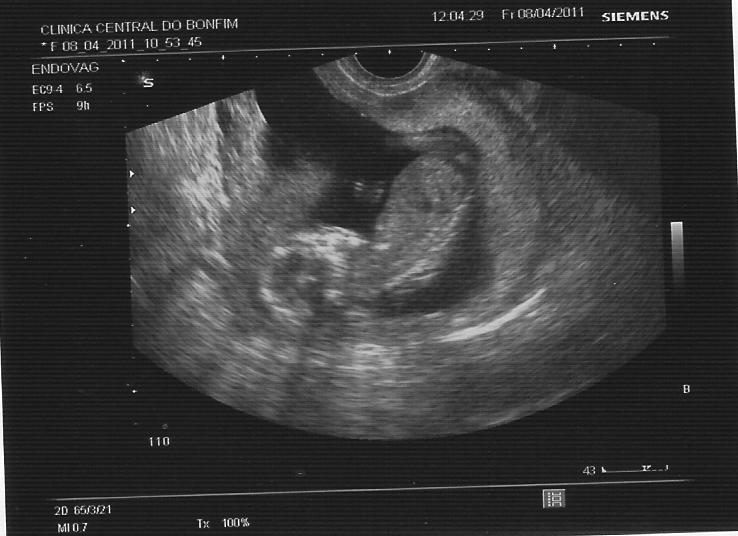

Deixo-vos aqui as fotos do nosso little alien.... a de cima de corpo inteiro, se é que se pode dizer isso, e de pernas pro ar! A segunda com o pormenor da suposta pila e a última com o fémur e o pé bem marcado! Enjoy....